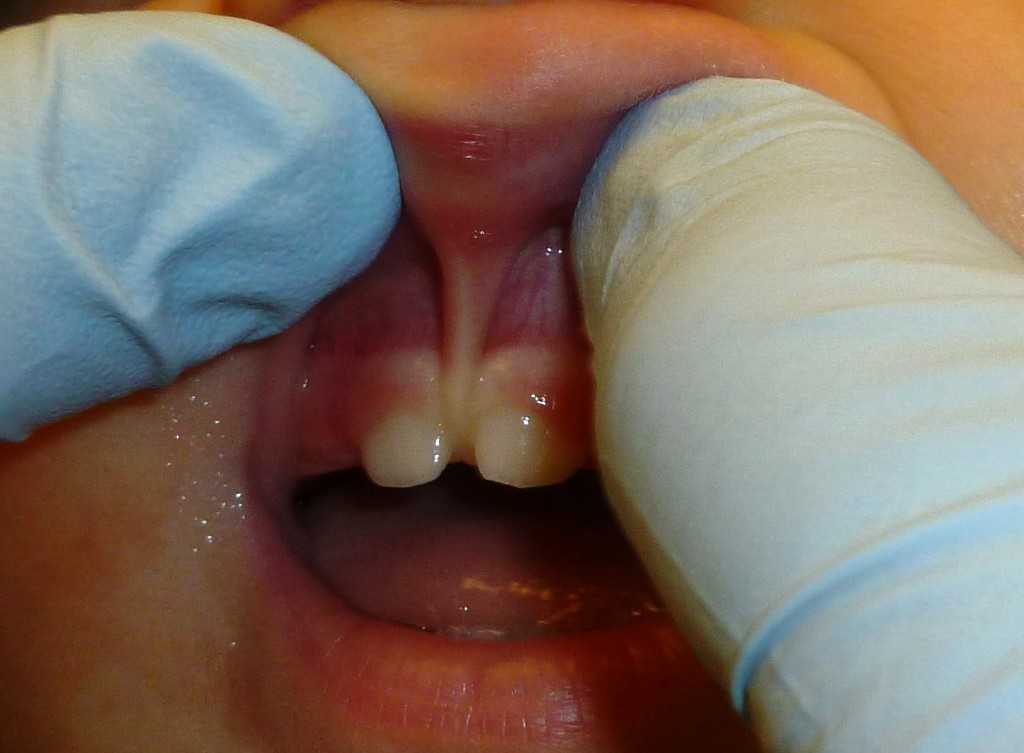

Lip Tie

Lip tie, released